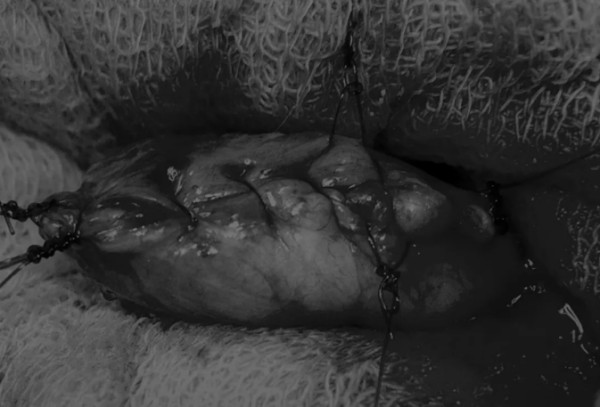

在牵引缝线之间选择血管扩张较差的区域用手术刀切开膀胱壁(图3)。在牵引缝合线之间用手术刀在血管不良的区域做切口。切开膀胱壁后,膀胱内的手术可按手术方案实施,例如取出结石(图4)。

8张图带你解锁新技能——膀胱切开术(附手术视频)(图4)

图4 这张图显示了从膀胱中取出的大量结石